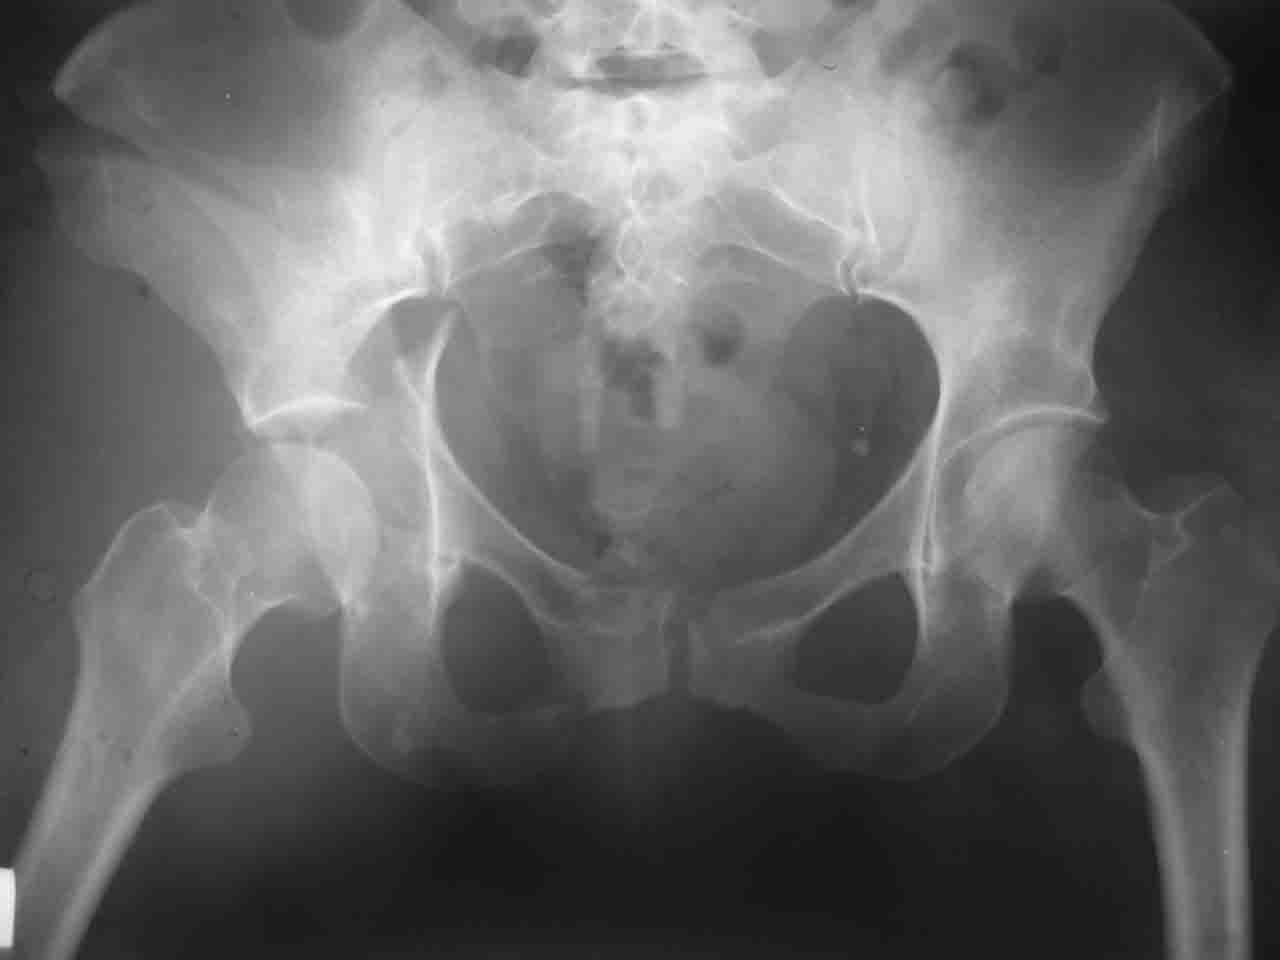

Интерес к реконструкции вертлужной впадины у меня появился довольно-таки давно, но до недавнего времени как-то не ощущалась готовность к практической реализации, а местный подход достаточно консервативен - перелом срастется,

а далее будет видно. Такую точку зрения я не разделяю, поэтому через конференции,ортофорум и свои случаи пытаюсь практически и теоретически *продвинуть* для себя тему реконструкции вертлужной впадины.

Логика подсказывает, что все-таки лучше иметь анатомически полноценную впадину, хотя ранее упоминалось состояние вторичной конгруэнтности и одно наблюдение у меня есть, когда у больного с полностью нарушенной анатомией впадины и подвывихом головки бедра кзади и кверху боли отсутствовали при относительно достаточном для стиля жизни больного объёме движений. Но это только одно наблюдение и кроме перелома впадины у этогобольного была и тяжелая ЧМТ в анамнезе. Основываясь на формулировке структуры ацетабулюм Э. Летурнеля - как перевернутой буквы Y, впадина для полноценной функции сустава должна иметь сферичность, соответствующую размеру головки бедра и если один из компонентов в дефиците, то функциональные последствия рано или поздно проявятся.

Сложностью, ассоциативностью характера перелома, я бы с радостью воспользовался мининвазивной перкутанной фиксацией винтами, но боюсь, что результат был бы ещё хуже, техникой непрямой репозиции перелома не владею, поэтому пытаясь получить анатомичную впадину приходится широко открывать, по крайней мере пока, а дальше буду пытаться уменьшать пространство...

Илеофеморальный доступ не совсем передний и сравнительно с илеоингвинальным, и Кохера-Лангенбека открывает весь наружный таз кроме самых передних отделов лонных костей, фиксацию которых я не ставил в задачу. Обширность диссекции, большая длительность операции и более высокий риск гетерооссификации - отрицательные моменты в обмен на возможность легче ориентироваться.

Вопрос доступа к вертлужной впадине при остеосинтезе задача не простая. Конечно, у Летурнеля и Тайла всё давно описано, нам остается только брать на вооружение. Но сами понимаете, что не бывает двух одинаковых ситуаций, поэтому в каждом случае вопрос решается сугубо индивидуально. Наша главная цель - восстановить анатомию с нанесением минимальной дополнительной травмы тазобедреннному суставу, думаю с этим никто не поспорит. Расширенный илиофеморальный доступ уж слишком травматичен (как сказал один коллега "таз лежит отдельно, больной отдельно").Стоит ли делать из пациента анатомический препарат для того чтобы легче ориентироваться. Да и нужно ли собирать всю "мозаику"? Мы применяли при таких операциях своеобразную операционную хитрость - сначала устраняли грубое смещение крыла под гребнем с фиксацией так называемой "плавающей" пластиной (временно фиксированной на двух винтах)- доступ или продлевали боковой, или делали небольшой дополнительный разрез над гребнем. Это позволяло устранить грубое смещение и захождение отломков тела повздошной кости, что значительно облегчало репозицию и остеосинтез впадины над сводом. Основное внимание конечно же уделяли нагружаемому задне-верхнему отделу. Сообщите ваш адрес, пришлю схемы и рентгенограммы.